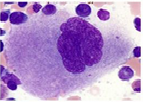

Figura 29. Megacarioblasto. Muestra: Médula ósea (MO)

Tinción: Wright. Aumento: 100x

Núcleo: Poseen un solo núcleo con dos o seis nucléolos (Rodak, 2007).

Citoplasma: Es escaso y azul no contiene gránulos (Rodak, 2007).

División: Pueden sufrir división nuclear y aumentar el volumen del citoplasma y alcanzar un diámetro de 50 µm (Rodak, 2007).

Maduración: Se convierte en promegacariocito (Rodak, 2007)